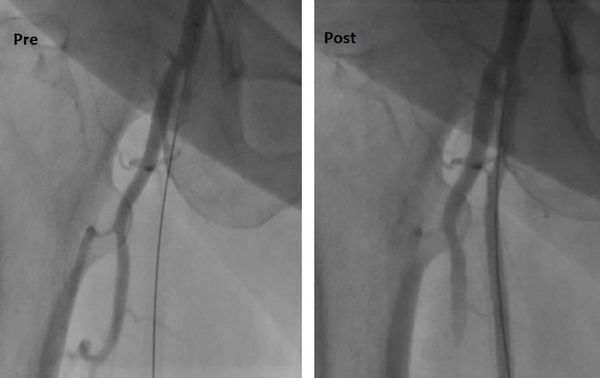

جراح أوعية دموية متخصص في علاج الوحمات الدموية للأطفال - انسداد الشرايين - قدم السكري والغرغرينا -علاج دوالي الساقين بالليزر

استشاري جراحة الأوعية الدموية و القسطرة التداخلية الطرفية